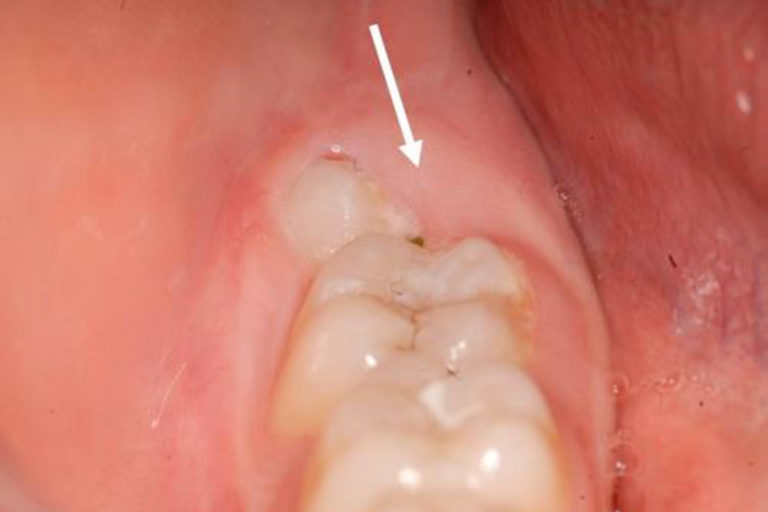

Recommandations d'extraction des dents de sagesse dans les cas suivants : • Lorsque le patient reflète une sensation de douleur ou d'inflammation des gencives, • Lorsque l'éruption de la molaire a été une source d'infection ou que le patient présente des kystes dentaires ou des tumeurs de la mâchoire, • Lorsque la dent de.. Mieux vaut peser le pour et le contre avant de prendre la décision de les retirer. Au nombre de quatre - deux sur la mâchoire du haut, deux en bas - les dents de sagesse apparaissent en général entre 18 et 24 ans. Ce sont nos troisièmes et dernières molaires, les premières poussant à l'âge de 6 ans et les deuxièmes à 12 ans.